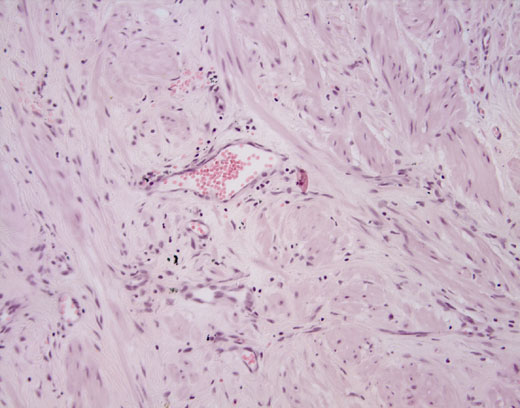

Cross-section #51 - 20X

click on the slide photo to see 40X magnification